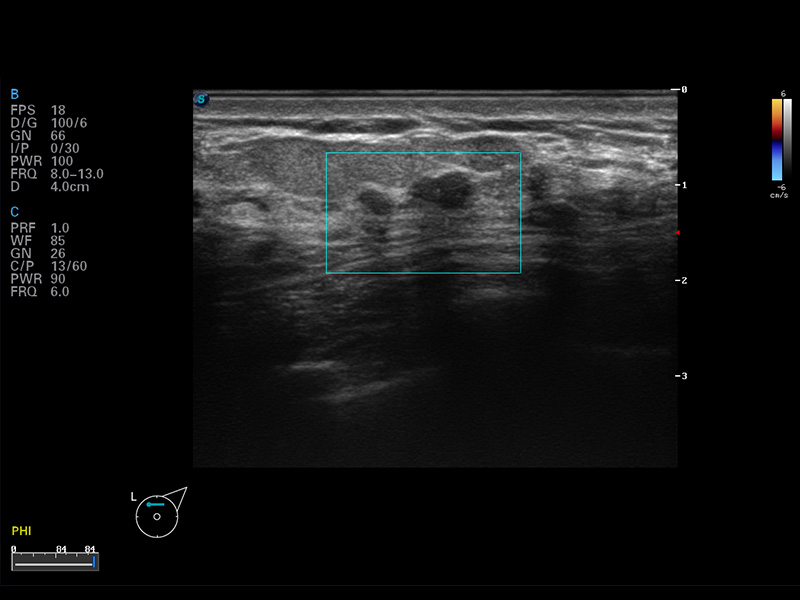

成像技术

多波束形成器

μ-Scan微米成像

谐波成像

空间复合成像